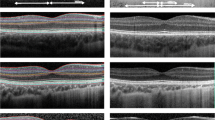

Macular vascular density (MVD; mm/mm2) in the superficial central area, macular vascular flow (MVF; %) in the superficial central area, foveal avascular zone (FAZ) area (mm2), and FAZ circularity were obtained from OCT-A images using the AngioPlex Metrix software. In addition, circumpapillary retinal nerve fibre layer (RNFL) thickness (µm) and macular inner plexiform ganglion cell layer (IPGCL) thickness (µm) were automatically quantified and obtained from OCT images (Fig. 1).

For eyes in which blood vessels crossed the fovea, the FAZ area was set to zero (Fig. 2). Mean central macular thickness (CMT; µm) in the fovea was obtained using the macular cube 512 × 128 protocol, where macular thickness data are presented in nine ETDRS areas. The central subfield (A1) measures 1 mm in diameter and was used to calculate CMT. Central retinal thickness (CRT; µm) was measured manually from the inner limiting membrane to the retinal pigment epithelium (Fig. 1).

Illustration of the OCT parameters extracted for analysis. A OCT-A image with the foveal avascular zone (yellow area) and the central macular thickness measured in 1 diameter (blue area). B OCT B-scan image of the retina with the central retinal thickness (green line) measured from the inner limiting membrane to the retinal pigment epithelium, the retinal nerve fibre layer thickness (red area), and the inner plexiform ganglion cell layer (blue area)